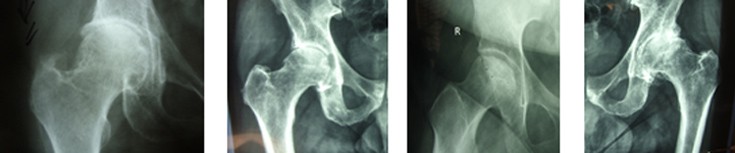

Η οστεοαρθρίτις του ισχίου είναι η κατάληξη όλων των παθήσεων που έχουν ήδη αναφερθεί, δηλ. του συγγενούς εξαρθρήματος, της δυσπλασίας, του CAM, της επιφυσιολίσθησης, του Perthes, της φλεγμονής, του υποκεφαλικού κατάγματος (που διαταράσσει την κυκλοφορία αίματος της κεφαλής), του κατάγματος της κοτύλης, του εξαρθρήματος του ισχίου.